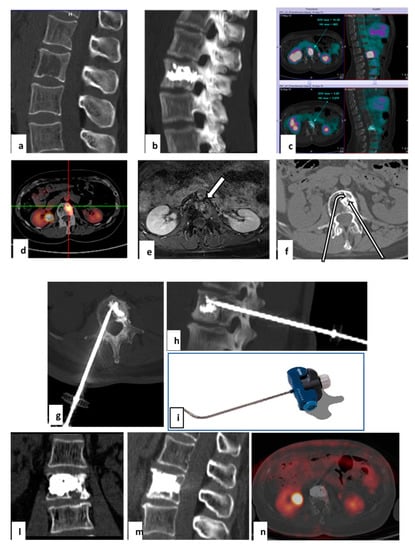

Figure 4. Treatment with tRFA and VA of a recurrent metastasis in a 57-year-old woman with a single L2 lytic metastasis from breast cancer. The metastasis had been treated previously with microwave ablation. Sagittal CT reconstruction showed a large lytic metastasis of L2 treated with microwave ablation (a). Sagittal CT obtained with MIP technique demonstrated the results of vertebral augmentation (b). PET-FDG performed before and 4 months after treatment demonstrates complete absence of metastasis uptake (c). Vertebral tumor recurrence 12 months after the microwave ablation treatment. FDG-PET demonstrated intense uptake of the vertebral body, anterior to the cemented area (d). T1 MRI with fat suppression acquired after gadolinium infusion revealed an area of contrast enhancement related to recurrence (e). Cement interposition hindered access to metastasis by left transpeduncular route with straight needle (straight arrow). The lesion can be reached by contralateral transpeduncular approach with a steerable needle (tSTAR) (f). Axial and coronal CT scans reconstructed with MIP technique (g,h) after tRFA navigation system placement (i). Coronal and sagittal CT scans after treatment of the second vertebroplasty (l,m). PET-FDG performed after 6 months demonstrates absence of metastasis uptake (n).